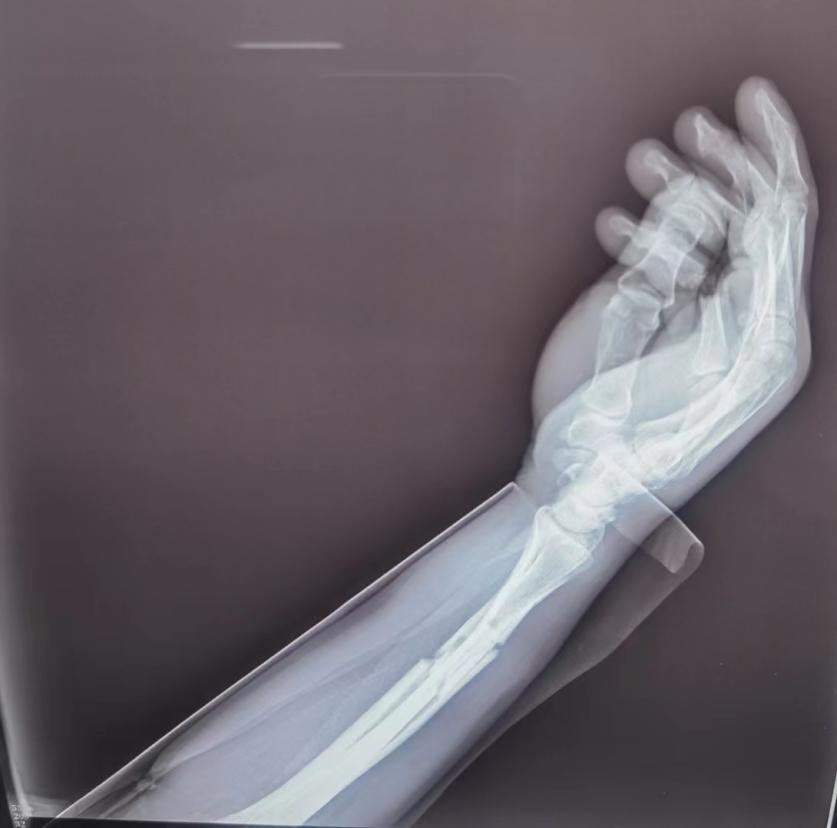

哈尔滨市骨伤科医院经常收治摔伤手腕的患者,如果不慎摔伤手腕,接下来该怎么能判断自己的伤情,又有什么值得注意的呢?以下几点建议可供参考:

伤后首先可以尝试自我诊断,初步判断病情的轻重

手腕挫伤后,请不要“揉捏”。如果是单纯的腕关节扭伤也许影响不大,但如果出现骨折的情况下,反复的“揉捏”在造成疼痛的同时,还可能导致骨折移位,加重病情。为了判断病情,可尝试轻微握拳、旋转手腕,可能会出现以下两种情况: